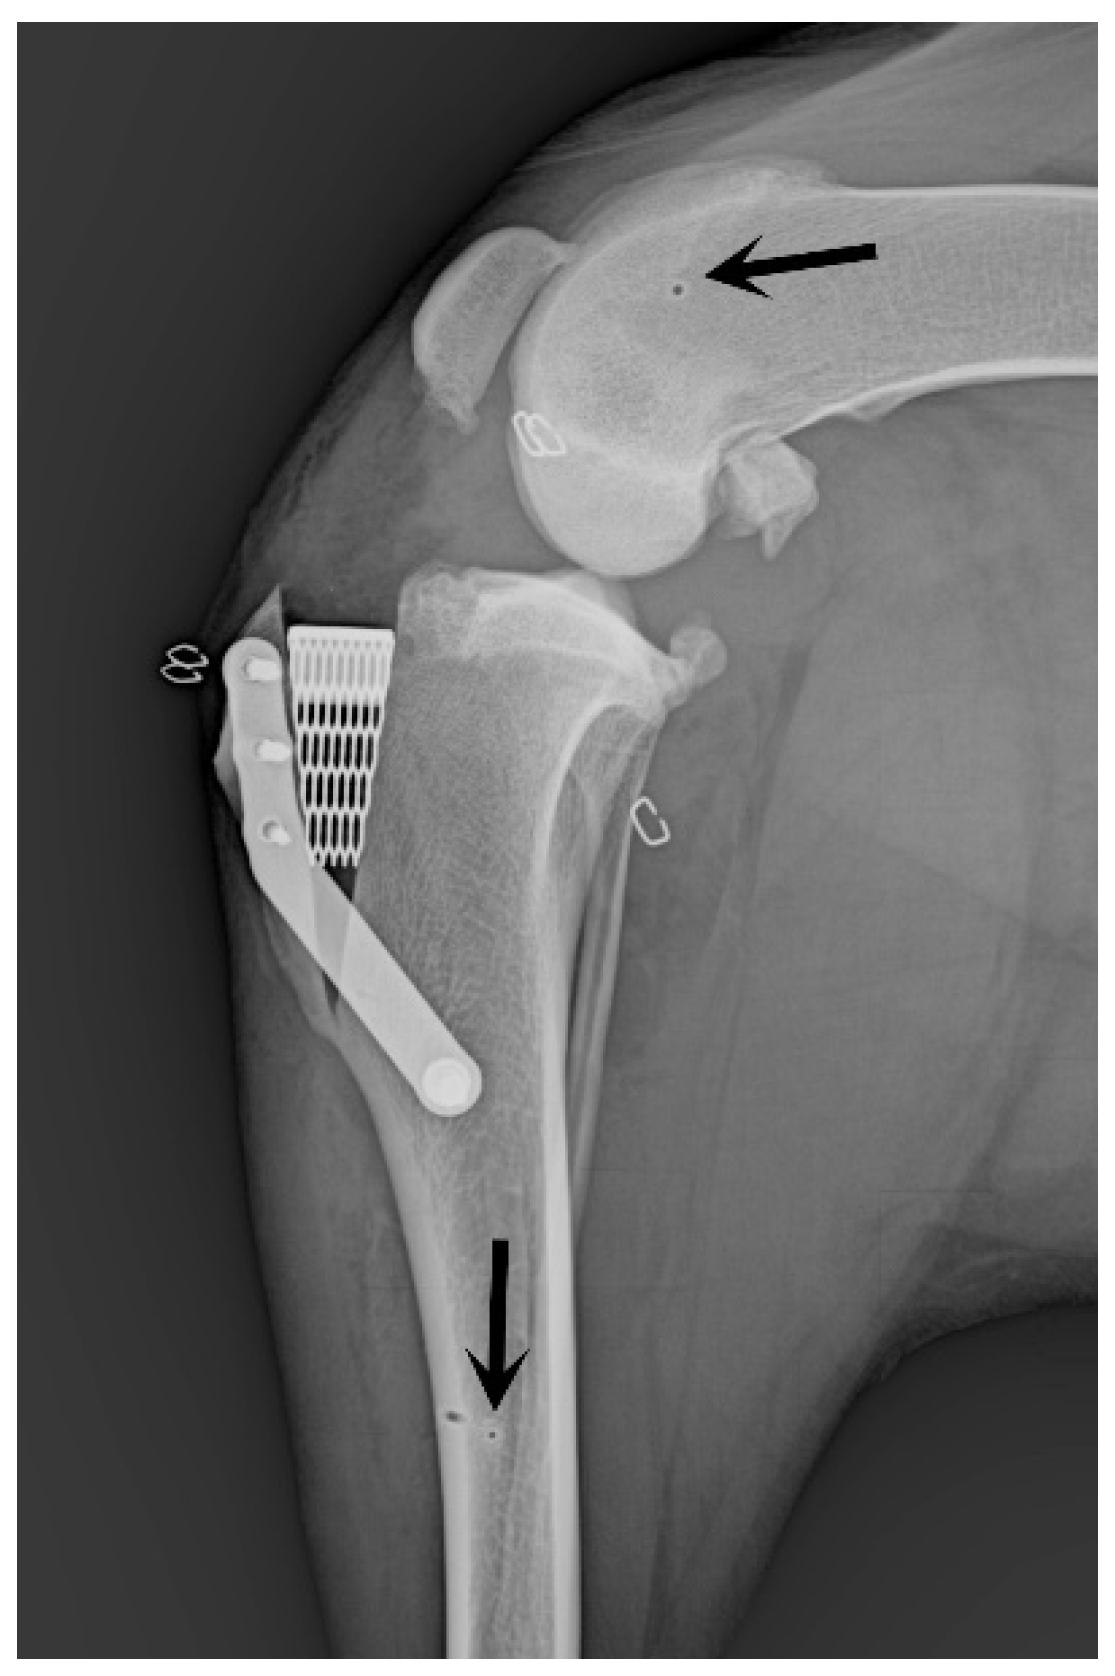

Figure 4. Postoperative X-Porous TTA mediolateral radiographic projection. Note the small holes due to the K wires of the traction stirrups connected to the Titan distractor.

2.4. Surgical Stabilization of the Stifle Joint

The stifle joint underwent surgical stabilization to treat cranial cruciate ligament injuries, employing the X-Porous tibial tuberosity advancement (X-Porous TTA) procedure [10] (implants: Ad Maiora, Cavriago, Italy). Post-surgical assessments included radiographic evaluations for all cases (Figure 4).

Following meniscal repair, a X-Porous TTA (modified tibial tuberosity advancement) procedure was routinely performed in all dogs to restore stifle stability. Postoperative tibial compression test was negative in all dogs.

Postoperative clinical rechecks revealed no complications associated with the meniscal repair technique. One dog presented a tibial fracture one month after surgery for a reason unrelated to the study. The fracture was subsequently treated with plate osteosynthesis.